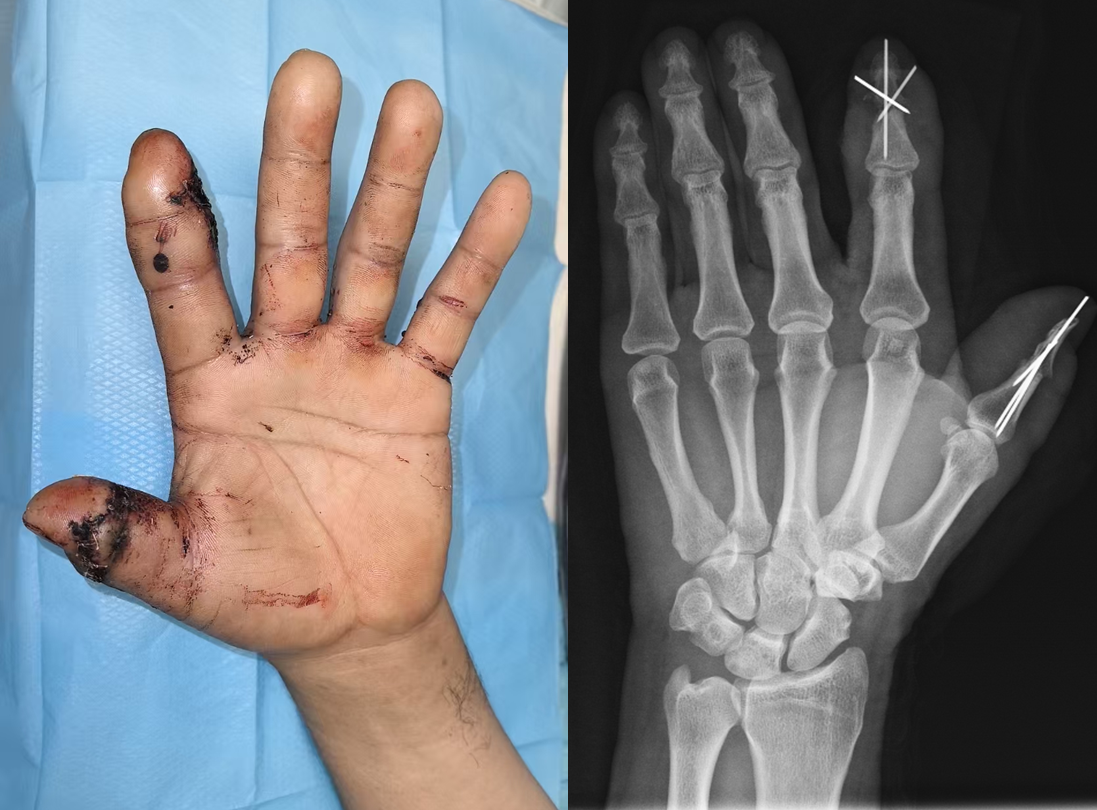

近日,苏大附四院骨科团队成功完成一例高难度左手拇指离断的再植修复手术,这是我院在显微外科与创伤修复领域实现的重大突破。术后患者再植拇指末梢血运良好、创缘愈合完全,已顺利出院。

断指再植手术需要极其精细的操作,需在直径不足1.2mm的指动脉上完成端端吻合,并同时重建拇指的静脉回流及神经支配;食指背侧的皮肤缺损则通过精准转移带血管蒂皮瓣覆盖骨外露创面。苏大附四院骨科王亮副主任医师、潘明铭主治医师等医疗团队成员密切合作,采用高倍显微镜下“血管神经束优先吻合”策略,术中探查发现高速电锯引起软组织挫伤严重,同时拇指动脉较细、动脉痉挛明显。医疗团队凭借精妙的显微外科技术,克服了手术中遇到的种种难题,实现动静脉通血“一次成功”。

术后苏大附四院医疗团队为患者制定“四防一促”管理方案:防血管危象、防感染、防血栓、防关节僵直、促神经再生。通过毛细血管反流监测、定制化抗凝方案及早期康复介入,患者再植指体顺利度过72小时血管危象高发期。目前,患者拇指及食指末梢血运良好,创口已愈合,提示再植的拇指及食指皮瓣存活。

患者术后左手形态基本恢复,拇指末梢血运良好,术后2周断指基本存活,复查X光片显示拇指及食指远节指间关节对合良好、形态基本恢复正常。